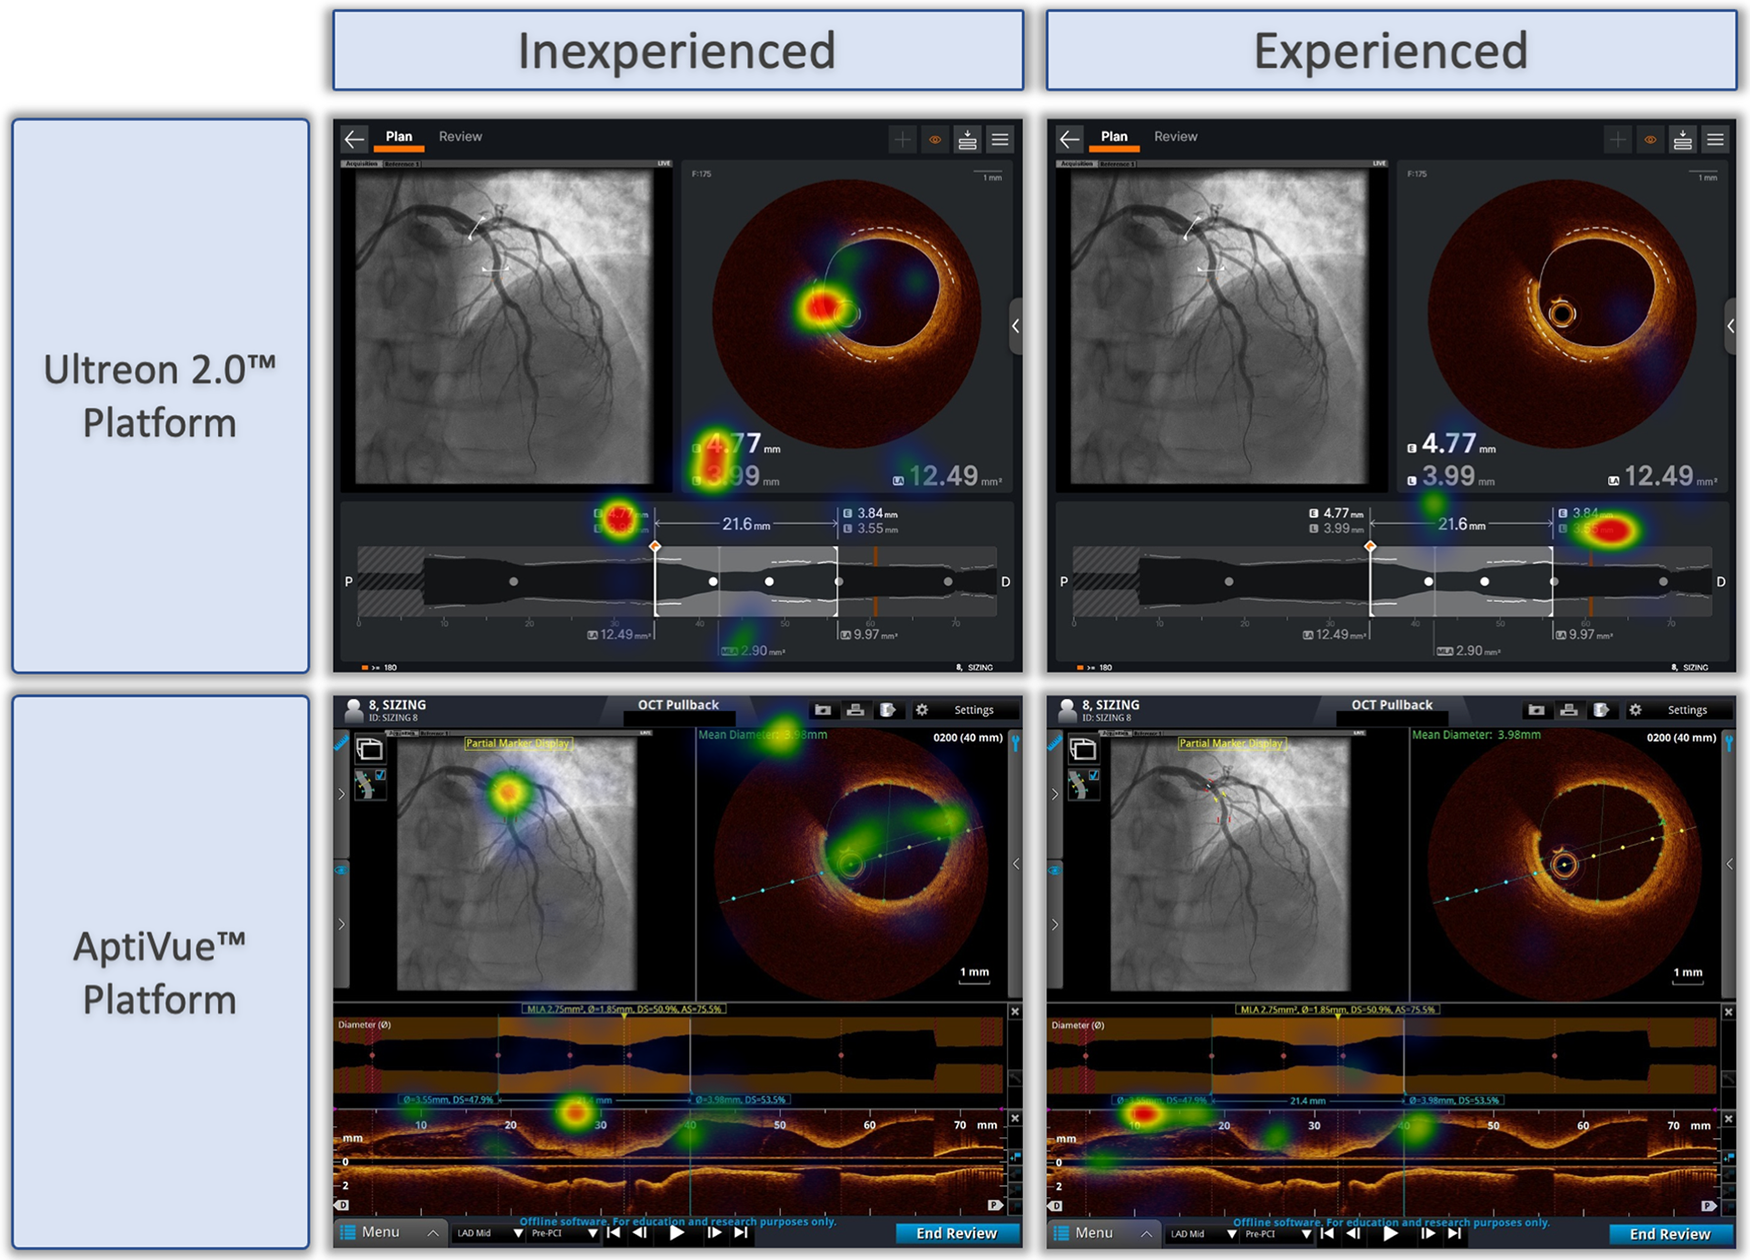

Qualitative review of heat maps showed fewer areas of focus in Ultreon™ 2.0 vs. AptiVue™ platforms and fewer areas of focus among experienced vs. inexperienced participants. A representative sample of heat maps for the stent sizing task is shown in Figure 4. Both experienced and inexperienced participants focused on key numbers in the Ultreon™ 2.0 platform but had more areas of focus in the cross section and longitudinal view in the AptiVue™ platform.

Figure 4

Representative heat maps of eye tracking during OCT-guided stent sizing task with Ultreon™ and AptiVue™ platforms. Eye-tracking heat maps which identify areas of fixation, with warm colors reflecting longer duration of gaze, and colder colors less duration of gaze. Representative samples of inexperienced and experienced participants deciding on stent size based on OCT imaging using the Ultreon™ 2.0 and AptiVue™ platforms.